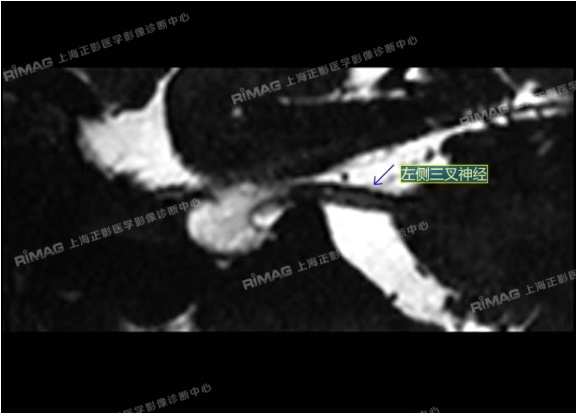

影像表现:右侧三叉神经根部外下方见小血管斜跨,与三叉神经分界不清;左侧未见明显异常(对照)。

MRTA:磁共振体层成像脑血管显影术,可清楚显示三叉神经与周围血管空间关系,为术前筛选、术中探查责任血管,提高手术疗效等提供了可靠的影像学依据。